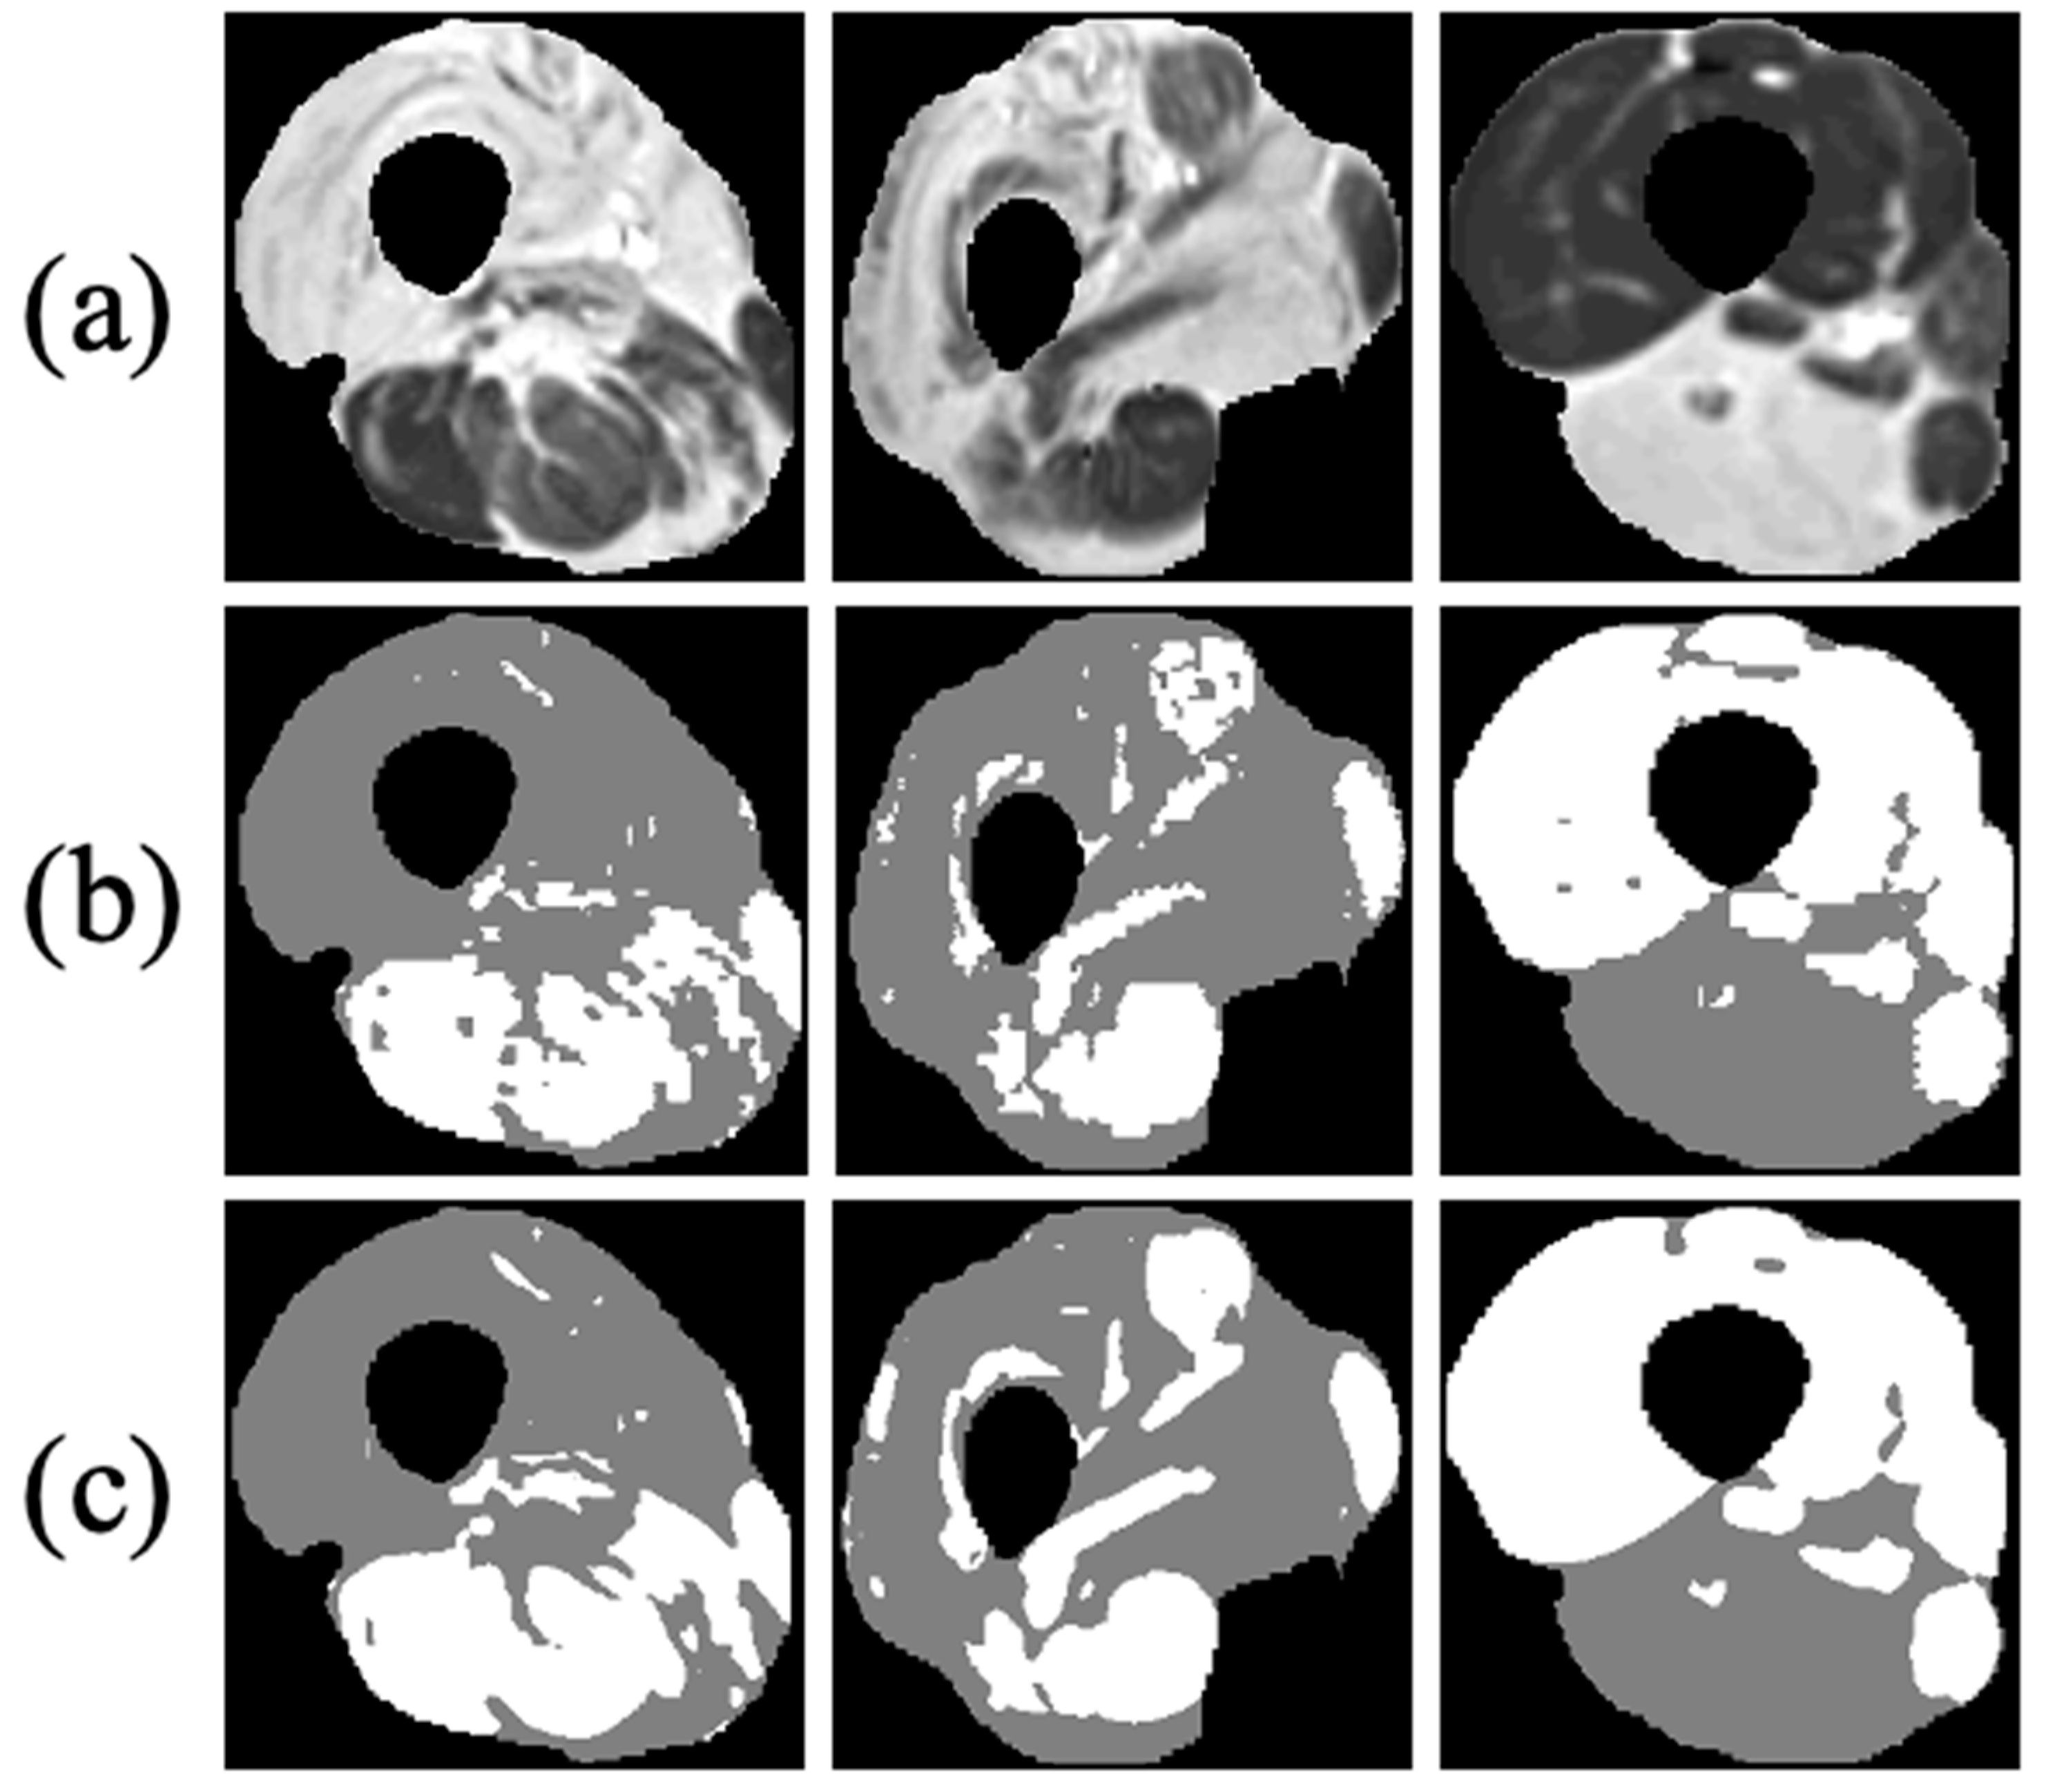

Muscle dystrophies (MDs) are an inherited class of disorders characterized by progressive muscle weakness that affects the upper and lower limbs, the axial muscles, and the facial muscles at variable levels of severity. Fat infiltration into muscles of the lower limbs is one of the hallmarks of these diseases’ progression and can be easily seen in MRI images. MDs lead to a loss of muscle mass and a weakening of muscle strength [1]. The infiltrated fat is usually referred to as intermuscular adipose tissue (IMAT) and is separated from the subcutaneous adipose tissue (SAT), which surrounds the muscle. The two fat tissues are separated by a boundary layer called “fascia lata”, used in many studies to achieve reliable segmentation of the lower limb anatomy (see Figure 1).

Figure 1. Axial MR image of the thigh. Red: fascia lata boundary; blue, green, and yellow arrows mark the subcutaneous fat, a region of viable muscle, and IMAT pixels.

Figure 8. Three examples of FCN-based classification of thigh anatomy: (a) axial MR images of three different patients after applying the first stage of the proposed method and segmenting the muscle region; (b) ground truth of the intermuscular adipose tissue (IMAT) and viable muscle pixels within the muscle region (white: viable muscle: gray: IMAT pixels); (c) tissue classification using the suggested FCN processing.

The results of the different clustering methods explored are presented in Table 2 (stage 2 of the postprocessing pipeline). The proposed method—DCAETL with k-means—outperformed the competing methods in viable muscle Dice, IMAT Dice, accuracy, NMI, and ARI. In Figure 8, the visualization results of the clustering of viable muscle and IMAT are shown, the classification was shown only on the muscle region that was segmented in stage 1.